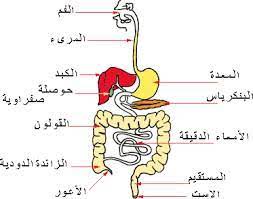

يتكون الجهاز الهضمي من مجموعة من الأعضاء التي تعمل بتناغم ودقة، تشمل الفم، البلعوم، المريء، المعدة، الأمعاء الدقيقة والغليظة، بالإضافة إلى أعضاء مساعدة مثل الكبد والبنكرياس. يلعب هذا الجهاز دورًا أساسيًا ليس فقط في هضم الطعام، بل أيضًا في التخلص من الفضلات، .وتنظيم مستويات السكر، وإنتاج إنزيمات ومواد ضرورية لصحة الجسم

الأعضاء الأساسية في الجهاز الهضمي

الأعضاء المساعدة في الجهاز الهضمي

الكبد

البنكرياس

المرارة

التكامل بين الأعضاء

:تعمل الأعضاء الأساسية والمساعدة بتناغم لتسهيل عملية الهضم

.تبدأ من تقطيع الطعام في الفم-

.يتم نقله عبر المريء ومعالجته في المعدة-

.يتم تفكيكه وامتصاصه في الأمعاء الدقيقة، وتنظيم المواد الغذائية بمساعدة الكبد والبنكرياس-

.أخيرًا، يتم التخلص من الفضلات عبر الأمعاء الغليظة والمستقيم والشرج-

يستعرض هذا الكتاب الجهاز الهضمي، أحد أهم أجهزة الجسم، الذي يحول الطعام إلى طاقة وعناصر غذائية ضرورية للحياة. يتناول الكتاب شرحًا لأعضائه الأساسية مثل الفم، المريء، المعدة، الأمعاء، والمستقيم، إضافة إلى الأعضاء المساعدة كالكبد، البنكرياس، والمرارة.